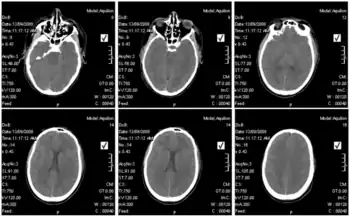

Blood tests of those infected revealed elevated liver values, white blood cell counts that were first low and then elevated over time, and low platelet counts.[8]In terms of the diagnosis of Lujo hemorrhagic fever the following is done:[15][16]

- CT scan (in some cases)